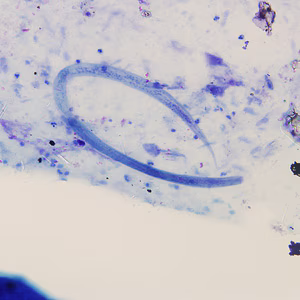

A 25-year-old man returned from three months of studying abroad in southeast Asia. Countries he visited during his studies included the Philippines, Indonesia and Thailand. Shortly after returning to the United States, he presented to his health care provider with abdominal pain, cramps and diarrhea.